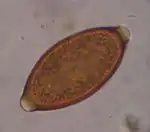

Trichuris trichiura, ou Trichocephalus trichiuris, est une espèce de nématodes (les nématodes sont un embranchement de vers non segmentés, recouverts d'une épaisse cuticule et menant une vie libre ou parasitaire). C'est l'un des parasites du tube digestif humain, dont des œufs fossilisés sont encore trouvés sur des lieux de fouilles archéologiques préhistoriques[1].

Détection

Ce parasite peut être mis en évidence par un examen parasitologique des selles chez le sujet infesté.